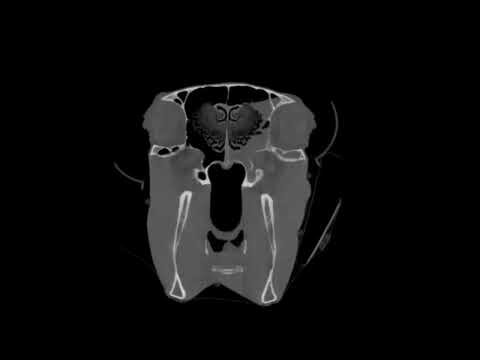

CT FINDINGS - ETHMOID HEMATOMA

CT images show a soft tissue mass in the left nasal cavity. This mass is intermittently associated with the left ethmoid turbinate and surrounded by soft tissue that has fluid attenuation and fills the surrounding sinuses. Right side is normal.

An ethmoid hematoma is a well-recognized but poorly understood disease in horses. Affected horses classically exhibit bloody nasal discharge originating from a hematoma-like mass within the ethmoid turbinates of the nasal cavity. source

The mass was removed through a frontonasal flap. The 3D reconstruction shows staples and sutures that closed the flap. Chester is reportedly doing well at home. Histopathology – findings consistent with ethmoid hematoma with bacterial colonies.

WHY IS CT USEFUL?

CT is useful in ethmoid hematoma cases where the mass cannot be viewed endoscopically because of the size or radiographically. CT scans provide a three-dimensional view of the hematoma and its relationship with adjacent structures. This helps surgeons plan the most appropriate treatment approach, whether it involves surgical removal or other therapeutic options.